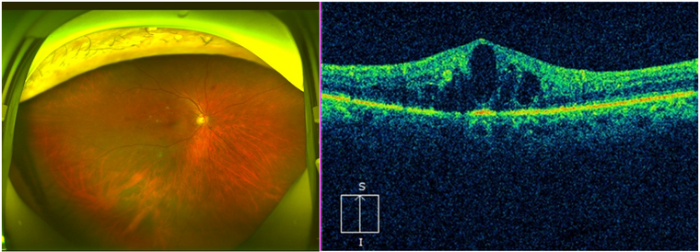

图:患者眼底检查显示视网膜散在微血管瘤,点片状出血渗出、黄斑区水肿明显

52岁的张叔叔(化名)患2型糖尿病10年,长期未规律监测血糖及眼底。日前因右眼突发视物模糊、视野中央出现扭曲变形就诊。经昆明艾维眼科医院眼底病科何雨檀主任检查发现,右眼视网膜散在微血管瘤,点片状出血渗出,黄斑区水肿明显,光学相干断层扫描(OCT)证实黄斑中心凹厚度达450μm,确诊为非增殖期糖尿病视网膜病变(NPDR)伴黄斑水肿(DME)。

“长期高血糖导致视网膜微血管渗漏和缺血,黄斑水肿是视力下降的主因。患者右眼视网膜大量出血,黄斑区严重水肿,视力仅剩0.1,若再延误可能导致永久失明。”何主任迅速制定 “抗VEGF药物+激光+血糖管控”联合方案。经3个月治疗,张先生双眼病情稳定,黄斑水肿消退,视力提升至0.5,生活自理能力显著恢复。